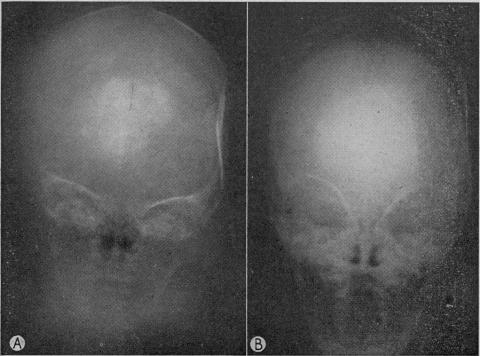

AXTON J H, LEVY L F

Br Med J. 1965 Jun 26;1(5451):1644-7. doi: 10.1136/bmj.1.5451.1644.